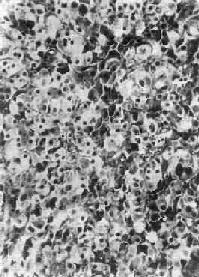

肾上腺皮质(adrenocortical carcinoma)甚少见,一般为功能性,发现时一般比腺大,重量常超过100g,呈浸润性生长,正常肾上腺组织破坏或被淹没,向外侵犯周围脂肪组织甚至该侧肾。小的腺可有包膜。切面棕黄色,常见出血、坏死及囊性变。镜下分化差者异型性高,细胞大小不等,并可见怪形核及多核,核分裂像多见(图15-17)。常转移到腹主动脉淋巴结或血行转移到肺、肝等处。分化高者镜下像腺,如果体小又有包膜,很难与腺区别,有人认为直径超过3cm者,应多考虑为高分化腺

图15-17 肾上腺皮质